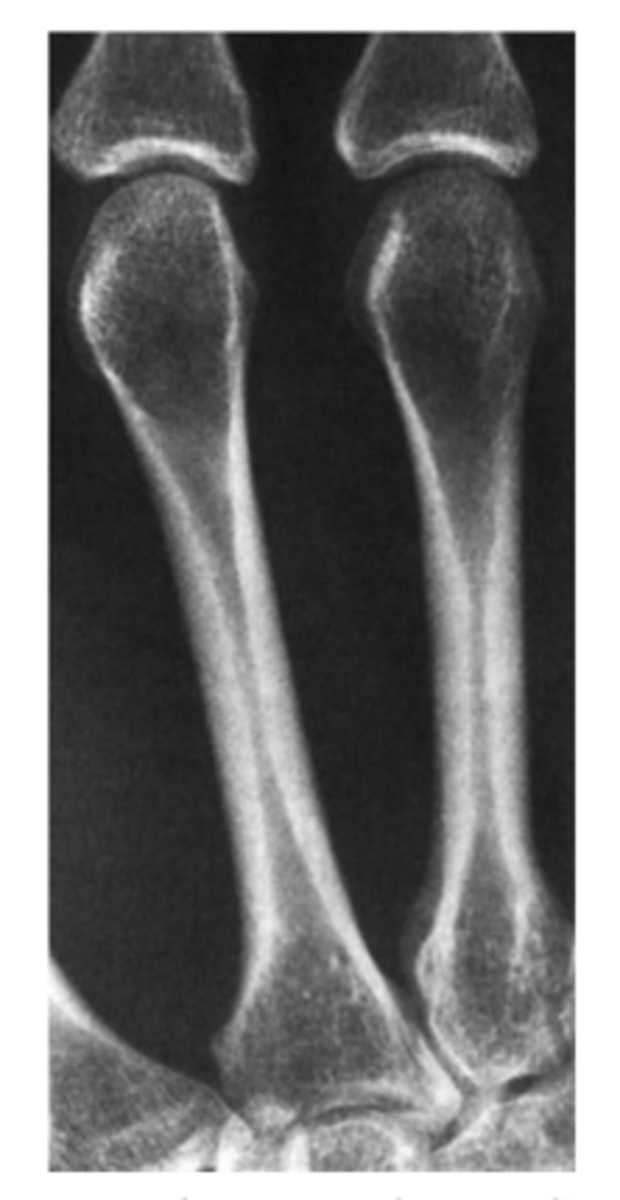

Anything abnormal with this image of the metacarpals? 36 y/o woman

Answer

Normal metacarpals!

Note the cortex is thick and homogenous in the mid shaft of the metacarpal. it bones thinner as it approaches the ends of the bones.